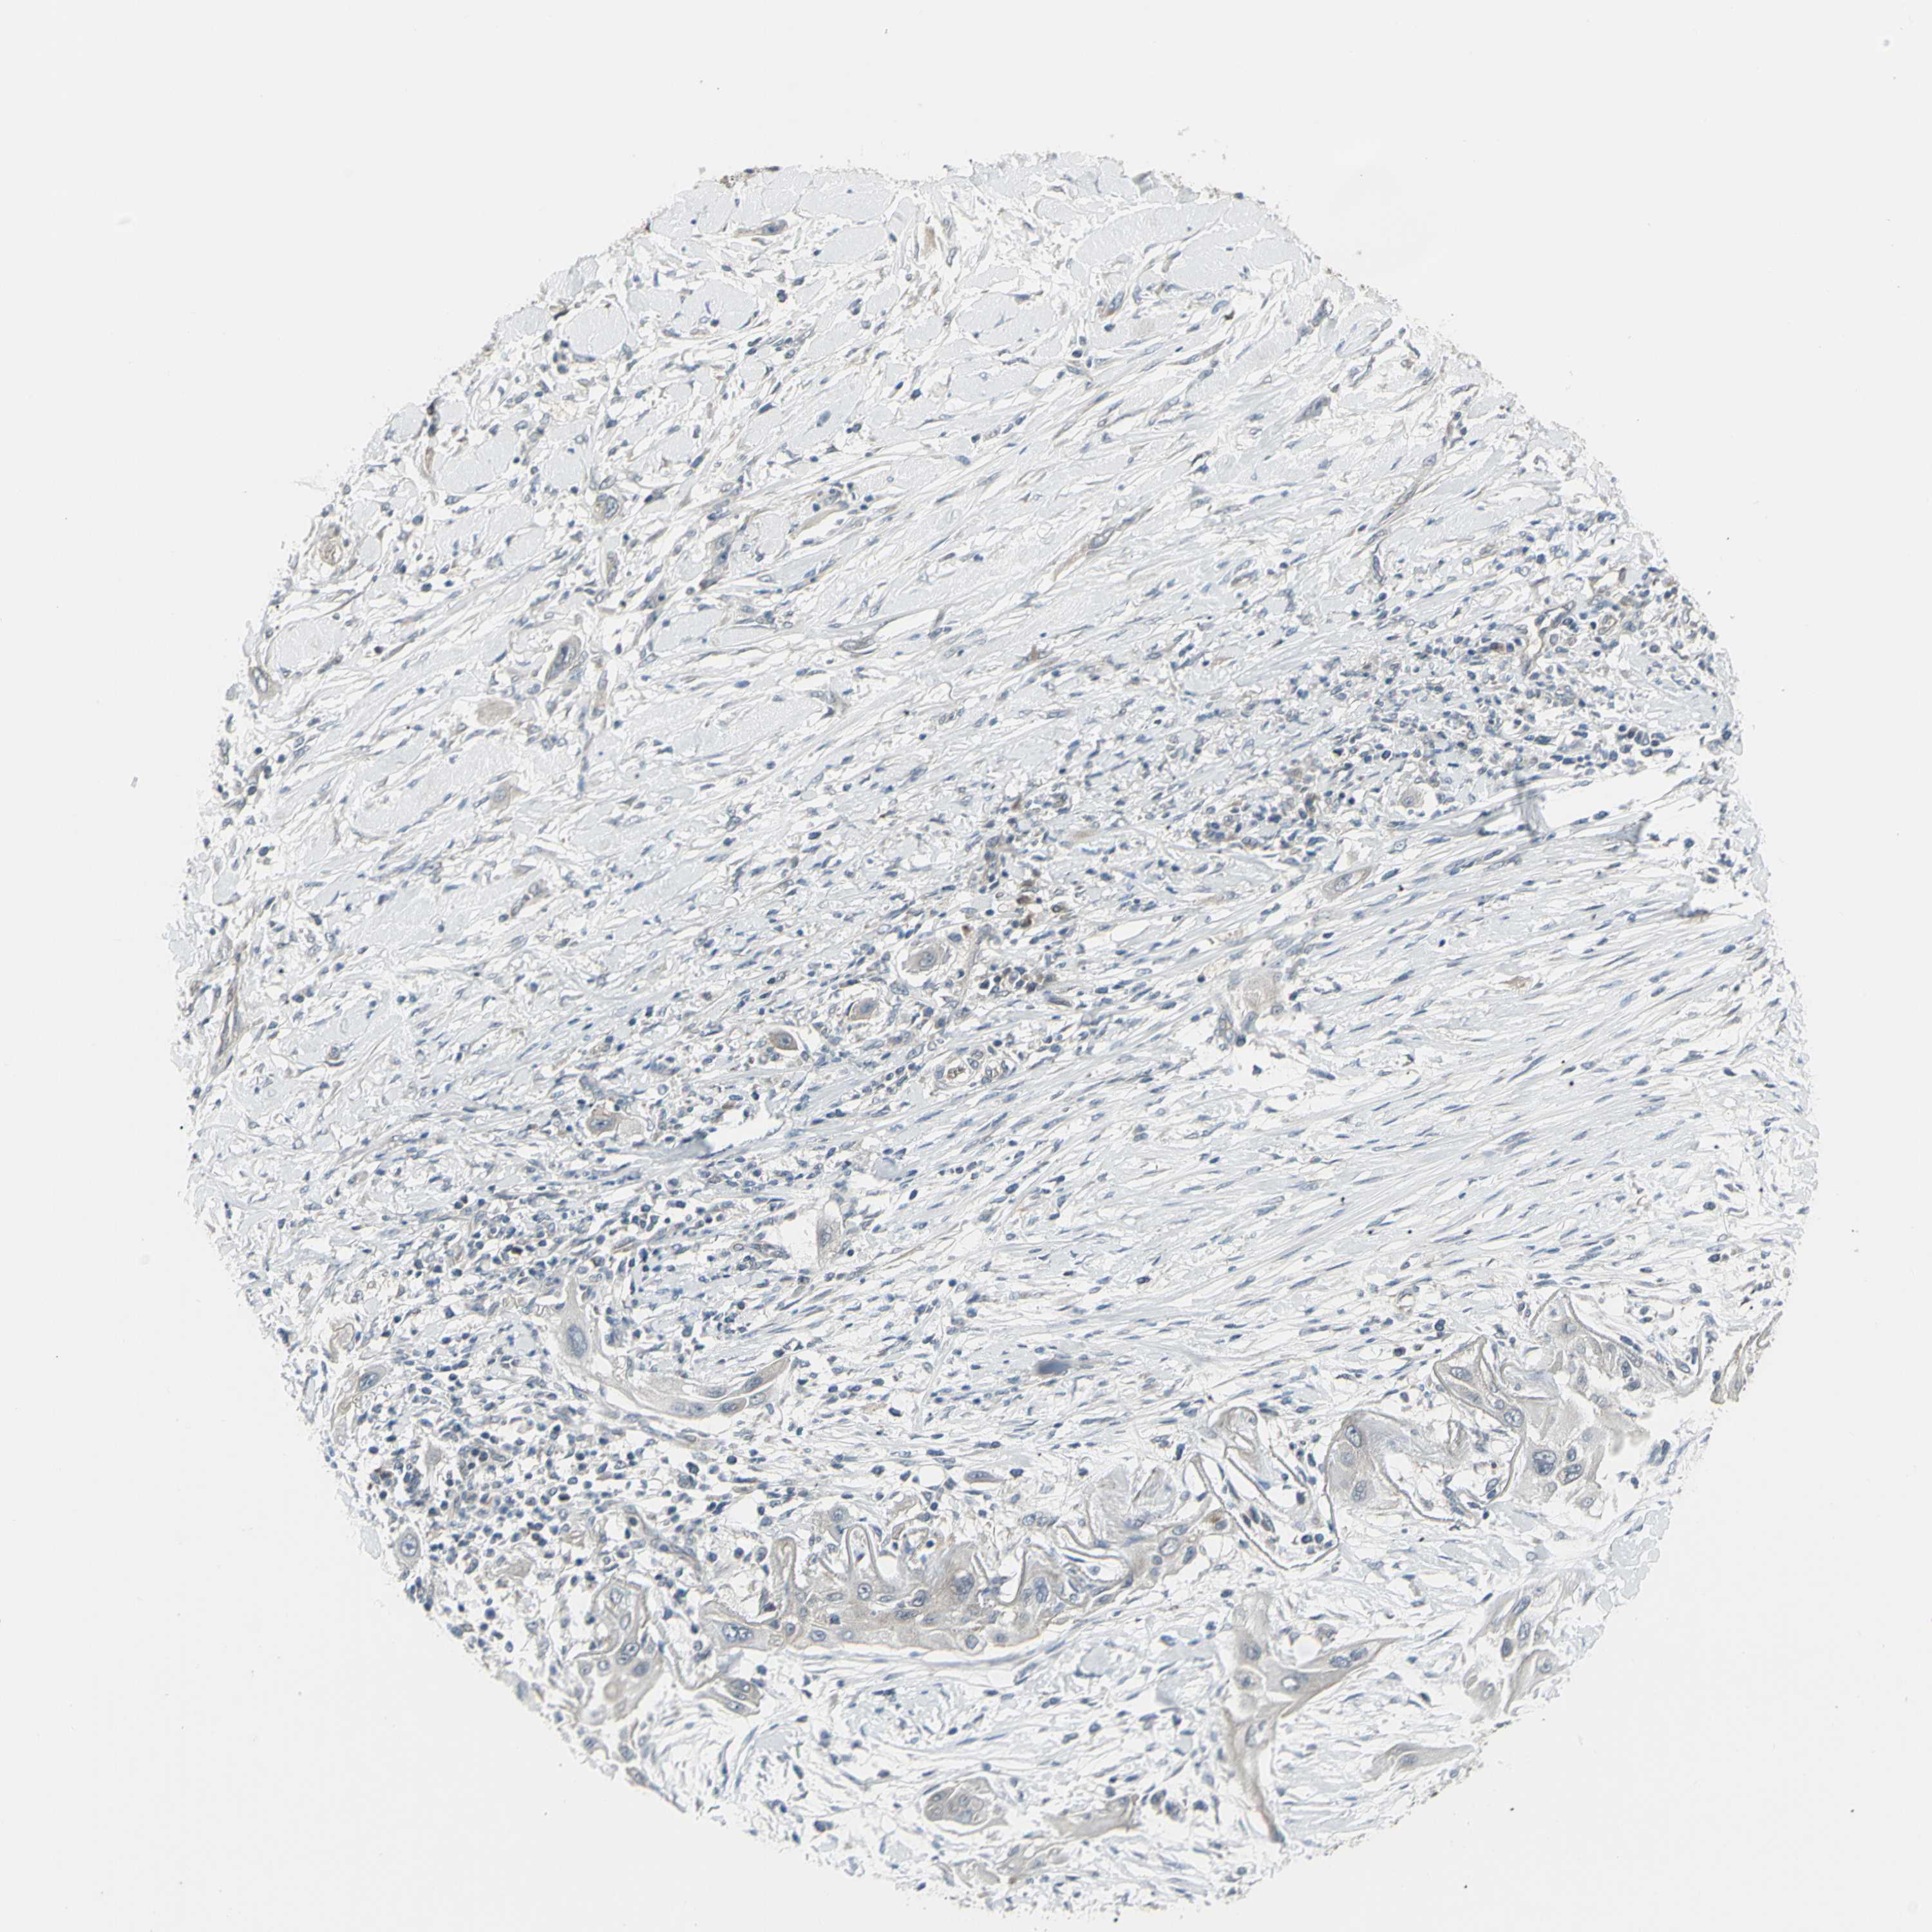

LUNG SQUAMOUS CELL CARCINOMA (TCGA) - Interactive survival scatter ploti

The Survival Scatter plot shows the clinical status (i.e. dead or alive) for all individuals in the patient cohort, based on the same data that underlies the corresponding Kaplan-Meier plots. Patients that are alive at last time for follow-up are shown in blue and patients who have died during the study are shown in red.

The x-axis shows the expression levels (FPKM) of the investigated gene in the tumor tissue at the time of diagnosis. The y-axis shows the follow-up time after diagnosis (years). Both axes are complimented with kernel density curves demonstrating the data density over the axes. The top density plot shows the expression levels (FPKM) distribution among dead (red) and alive patients (blue). The right density plot shows the data density of the survived years of dead patients with high and low expression levels respectively, stratified using the cutoff indicated by the vertical dashed line through the Survival Scatter plot. This cutoff is automatically defined based on the FPKM cutoff that minimizes the p-score. The cutoff can be changed by dragging the vertical line or by entering a cutoff value in the square labeled "Current cut-off".

Under the Survival Scatter plot the p-score landscape (black curve; left axis) is shown together with dead median separation (red curve; right axis). Dead median separation is the difference in median mRNA expression between patients who have died with high and low expression, respectively. It is calculated as follows: median FPKM expression of dead patients with high expression - median FPKM expression of dead patients with low expression. This is intended to aid the user in visually exploring custom cutoffs and the associated p-scores and dead median separation.

Individual patient data is displayed and can be filtered by clicking on one or more of the category buttons on the top of the page. Categories describing expression level and patient information include: high, low, alive, dead, female, male and tumor stages. The scale of the x-axis can be toggled between linear and log-scale by clicking on the "x log" button. Mouse-over function shows TCGA ID, patient information and mRNA expression (FPKM) for each patient.

& Survival analysisi

Kaplan-Meier plots summarize results from analysis of correlation between mRNA expression level and patient survival. Patients were divided based on level of expression into one of the two groups "low" (under cut off) or "high" (over cut off). X-axis shows time for survival (years) and y-axis shows the probability of survival, where 1.0 corresponds to 100 percent.

NAXD is not prognostic in Lung Squamous Cell Carcinoma (TCGA)

: 18.98

P scorei

N/A

Average pTPM 23.1

Number of samples 489